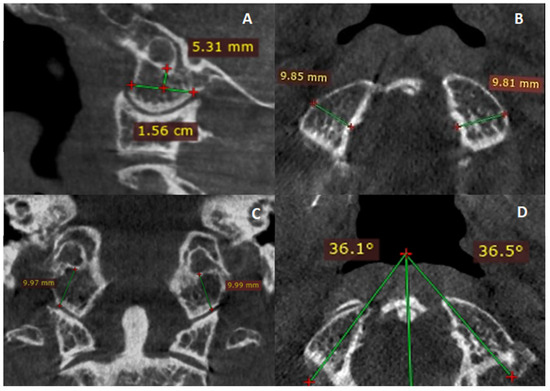

2. Materials and Methods